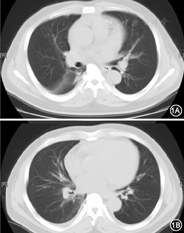

患者男,52岁。2015年3月患者因"慢性肾小球肾炎、慢性肾衰竭(尿毒症期)"行股静脉置管术,开始血液透析治疗。2015年4月患者改用动静脉瘘行血液透析,期间曾因"渗血"导致左前臂软组织轻度感染,口服头孢地尼后好转。既往高血压19年。2015年6月1日患者无明显诱因出现胸闷憋气,夜间不能平卧,伴低热(T 36.3~38.0℃),咳少量白色黏痰。体检:T 36.5℃,脉搏90次/min,呼吸20次/min,血压180/79 mmHg(1 mmHg=0.133 kPa); 双肺呼吸音粗,散在湿啰音,心率92次/min,律齐,主动脉瓣区可闻及舒张期杂音。腹平软,无压痛,肝脾肋下未及。双下肢轻度水肿。辅助检查:血白细胞9.4×109/L,中性0.719,红细胞3.18×1012/L,血红蛋白91 g/L,血小板210×109/L,血白蛋白35 g/L,尿素氮32 mmol/L, 血肌酐1 012 μmol/L,尿酸439 μmol/L,血钾5.77 mmol/L,ESR 40 mm/1 h,C反应蛋白19.2 mg/L,尿白细胞 (-), 尿蛋白 (+), 胸部CT示双肺片状影,小叶间隔增厚(考虑肺水肿),心影增大,双侧胸腔积液,心包积液(图1)。腹部B超:双肾缩小,未见其他异常。诊断:急性左心力衰竭,尿毒症。给予加强透析和超滤(体重减轻4%),患者胸闷、憋气和咳嗽消失,夜间可以平卧,双肺呼吸音转清,但患者仍低热。随后,给予连续3次外周血(不同穿刺点)培养(细菌和霉菌)和药物敏感试验,并行超声心动图检查,结果显示,主动脉瓣瓣叶增厚,左冠瓣与右冠瓣交界处明显增厚,右侧瓣膜可见0.3 cm×0.3 cm的赘生物附着,舒张期见中度偏心性反流,左心射血分数(LVEF)65% (此结果得到再次检查确认)。3次血培养结果均为棒状杆菌(双侧需氧瓶报警),经MALDI-TOF质谱鉴定为杰氏棒状杆菌。未见厌氧菌和霉菌生长。杰氏棒状杆菌在哥伦比亚血平板上呈浅灰白色,菌落极小,点状、光滑、不凸起,革兰染色为阳性杆菌,呈栅栏状排列。药敏试验结果对万古霉素、环丙沙星敏感(表1)。治疗给予万古霉素1.0 g/d静脉滴注。3 d后患者体温恢复正常,治疗4周后超声心动图检查显示主动脉瓣赘生物钙化。治疗结束7 d后外周血培养结果为阴性。随访至今,病情稳定。